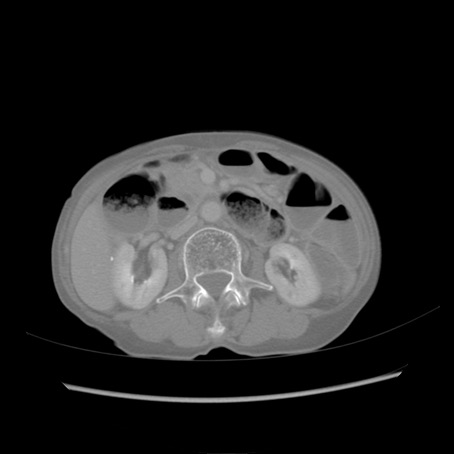

症例25(横断像)

【症例】80歳代女性

【主訴】胸のつかえ感

【現病歴】約9時間前に食後から胸のつかえた感じあり、嘔吐あり、来院。

【既往歴】胃癌(全摘)、胆摘、虫垂炎

【身体所見】心窩部に圧痛あり、反跳痛なし。

【データ】WBC 5700、CRP 0.05